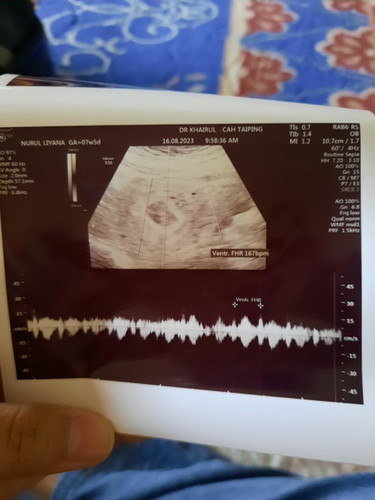

bersyukur sangat sangat. pagi ni scan 7w5d, dah ada jantung baby saya. first time dengar, happy sangat. kandungan ketiga saya 🥰 dua kandungan sebelum ni missed miscarriage. Alhamdulillah Allah bagi rezeki pada masa yang tepat. Percaya dengan rezeki Allah nak bagi ❤️ semoga membesar dengan baik, sempurna, sihat yaa anak mama 🥰 saya doakan semua orang dalam ni baby dalam kandungan sihat2 jaa.

perasaan kita sama🥰 dulu masa scan 6w+, nampak kantung je. doc suruh repeat scan utk tgk lagi. sedih dan risau sngt masa tu. alhamdulilah 13/8 haritu scan, nampak si kacang saya dgn jantung dia kelip2🥰 sebak masa tu. mulut tak benti ucap alhamdulilah. semoga allah jaga kandungan kita dalam keadaan yg baik2 sampai dia selamat lahir. take care mama🥰

Sy scan hritu 6w nmpk kantung je. Smlm scan lgi dh 8w nmpk jntung baby berkelip2 dgn dpt dgr heartbeat baby. Tp smlm scan tu dkt hosp terus sbb ada spotting. Dgr baby ok dlm kandungan rse terharu. Tp dr bagi ubat kuat rahim